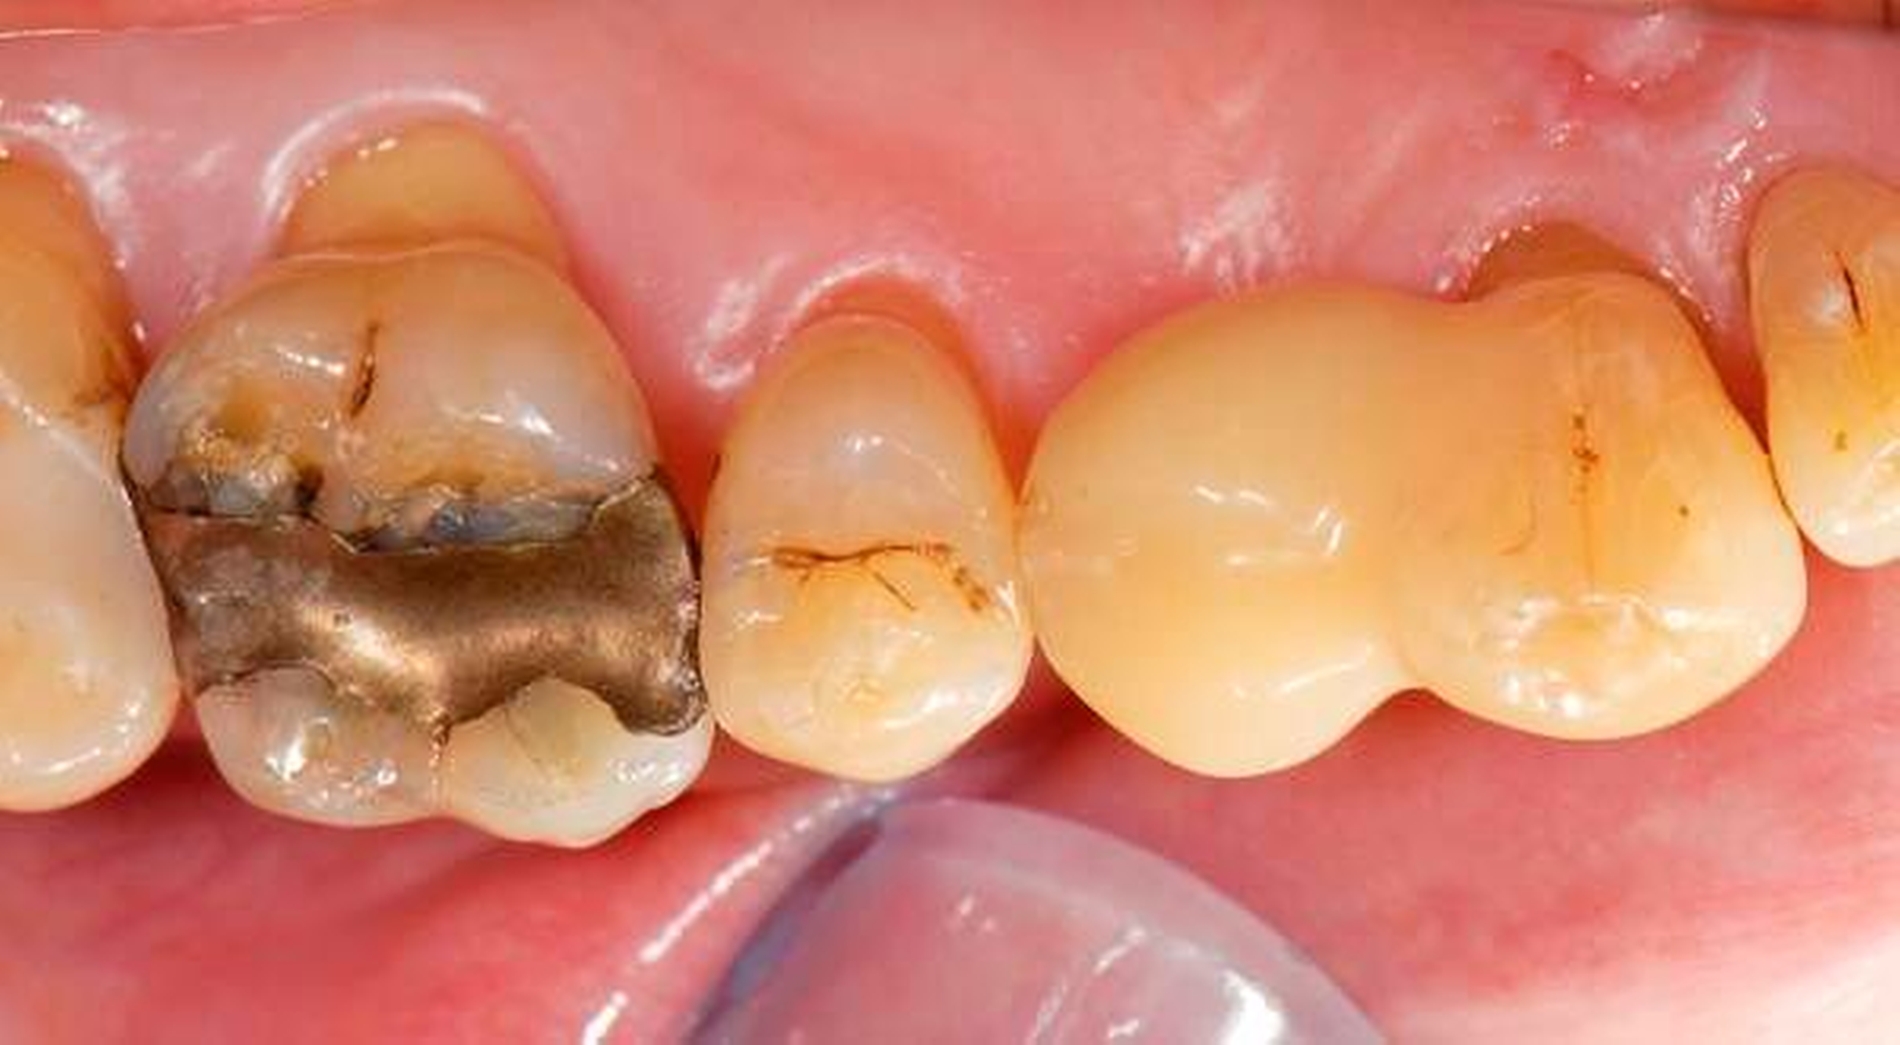

Abbildung 3: Direkte Reparatur im Seitenzahnbereich (R2-Technik)

In den Abbildungen 1 bis 3 werden Optionen für frugale Interventionen auf restaurativem Sektor aufgeführt. Es handelt sich um direkte Vollüberkronungen im Frontzahnbereich (hier: hergestellt in R1-Technik / einphasig) (Abbildung 1), direkte Teilüberkronungen im Seitenzahnbereich (hier: hergestellt in R1-Technik / einphasig) (Abbildung 2), Reparatur-Restaurationen im Seitenzahnbereich (hier: hergestellt in R2-Technik / zweiphasig) (Abbildung 3). Technische Einzelheiten zur Vorgehensweise und den Ergebnissen sind an anderer Stelle beschrieben (Literatur siehe oben).

schadensgerechte Reparaturtechniken (Abbildung 3),